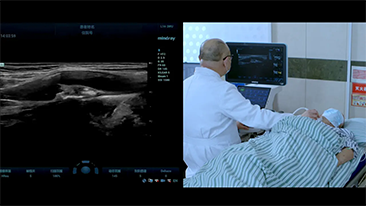

Covid-19: un momento critico per persone e dispositivi

A causa del Coronavirus, gli ospedali e il personale medico hanno sviluppato nuove pratiche di lavoro che comportano, nei contesti di assistenza acuta, il distanziamento sociale, l'uso rigoroso di dispositivi di protezione individuale (DPI), il lavaggio delle mani e la disinfezione quotidiana delle attrezzature. Le apparecchiature portatili, altamente mobili e versatili sono diventate sempre pi├╣ richieste nei punti di cura (POC), in particolare quando i reparti e le sale operatorie sono distribuiti su pi├╣ piani e lŌĆÖutilizzo di dispositivi specialistici ├© importante.